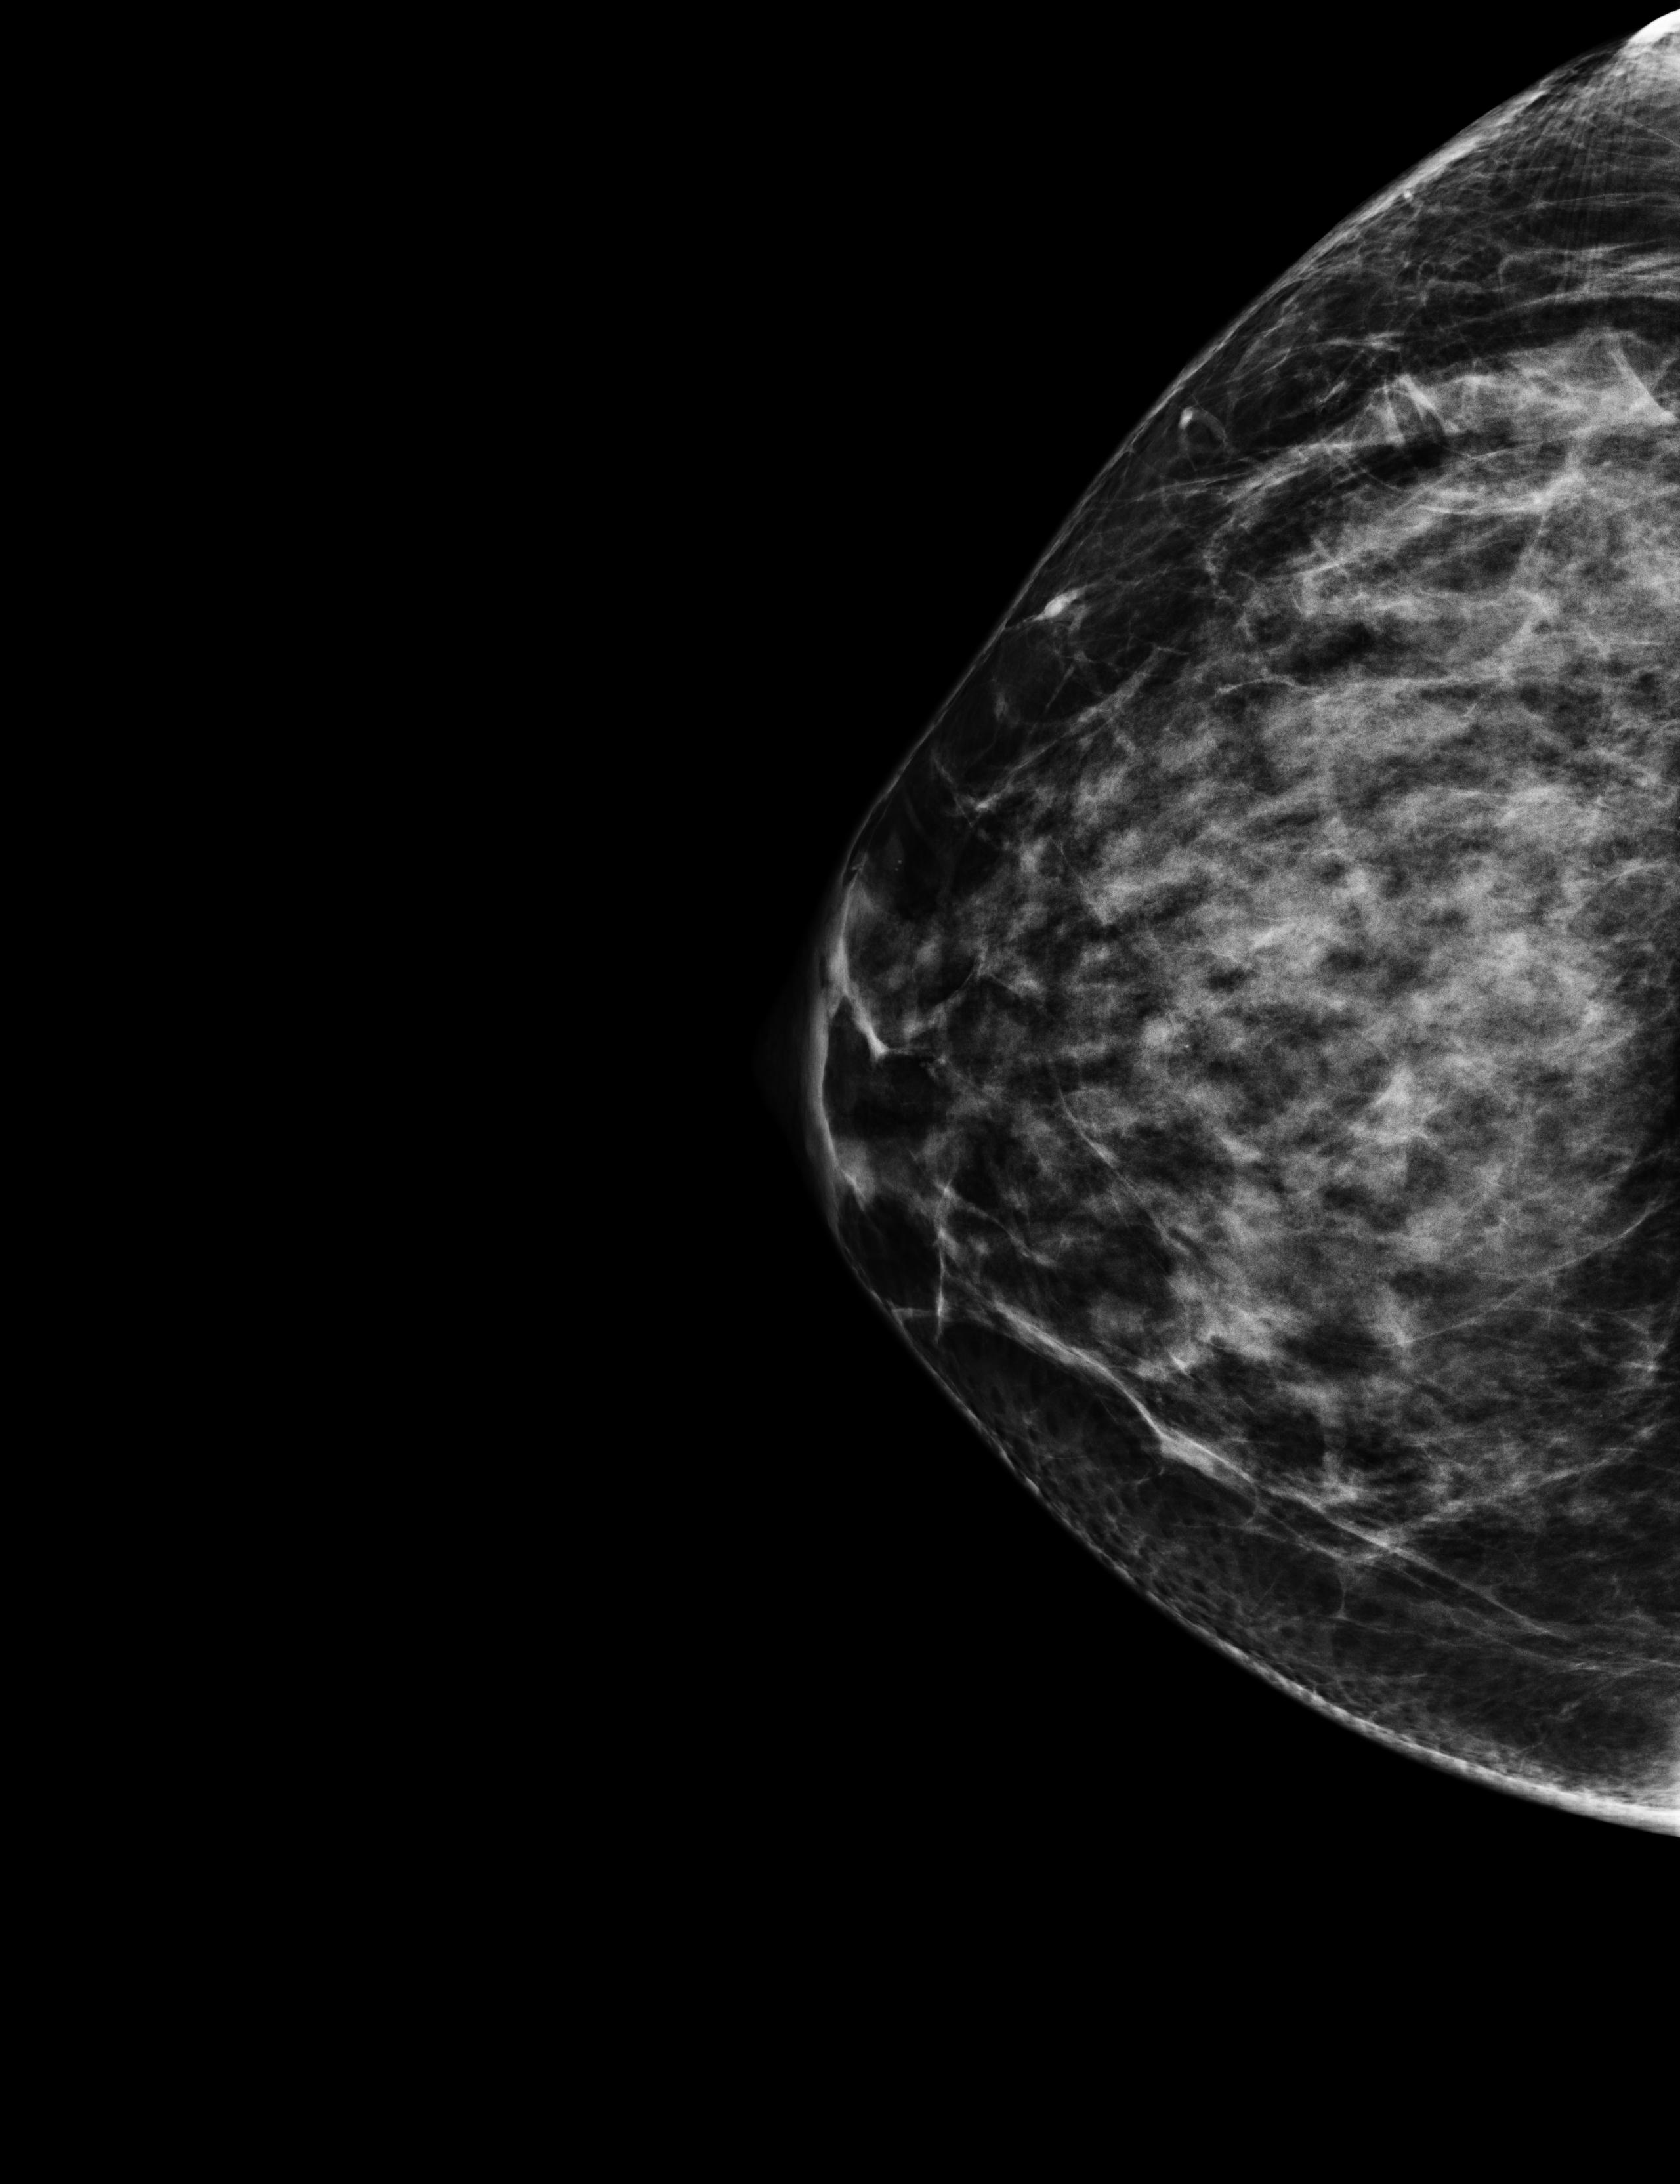

On October 17th 2023 I went to the hospital for an echography; the radiologist asked me almost immediately if they could perform a biopsy. So they stuck a needle in my breast and took out a few tissue samples. It was painful as hell and I ended up crying, confused, and trembling on the bed. The doctor asked me why I went alone for a check of this entity. Well, I didn’t know better, but there was my first lesson:

The data I chose for this day are two scans from the echography, they both clearly show the lesion; the second picture also shows the measurements the radiologist took.